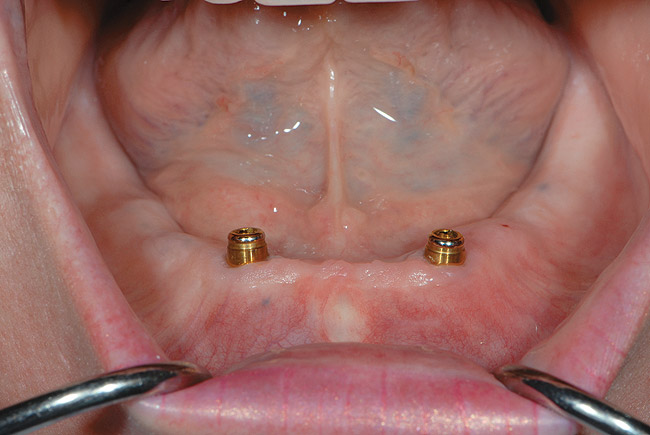

Figure 4  An example of a two-implant tissue bar for an implant-assisted prosthesis.

Figure 4

Figure 5  Locator abutments placed on implants can also be used for an implant-assisted prosthesis.

Figure 5

When dental implants were introduced by Brånemark, they were intended primarily for the completely edentulous patient, specifically the edentulous mandible. The initial prosthesis was a fixed restoration commonly referred to as a fixed bone anchored bridge. That particular prosthetic design is now the fixed-detachable hybrid prosthesis and has been highly successful for both the implants and prostheses.12,13 Implants have also been used for overdenture restorations14 and can be implant-assisted or implant-supported. With implant-assisted prostheses, the implants and mucoperiosteum share the forces of occlusion. A simple two-implant overdenture, either a Hader Bar® (Sterngold™, www.sterngold.com) or Locator® abutment (Zest Anchors, www.zestanchors.com), are examples of implant-assisted overlay prostheses and are always a removable restoration (Figure 4 and Figure 5). With implant-supported prostheses, the forces of occlusion are borne solely by the implants. This prosthesis can be an overlay prosthesis or a fixed restoration. Milled bar restorations, overdentures with bar substructures, and metal–ceramic restorations attached to implant abutments by either screws or cement are examples of implant-supported restorations. One of the primary benefits of using dental implants in edentulous patients is the preservation of the residual bone, which will provide a better opportunity for future successful prosthetic restorations.